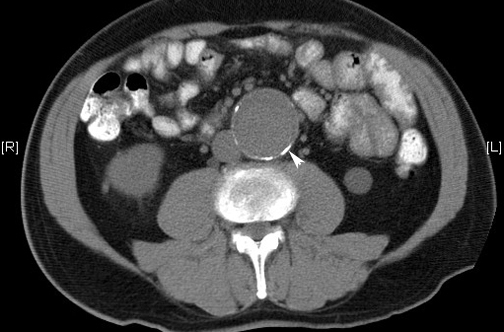

Hay un descenso de la incidencia de mortalidad en las últimas décadas que excede a los efectos del rastreo, y que vuelve menos claro el balance de los riesgos y los beneficios del cribado. The Lancet, 14 de junio de 2018